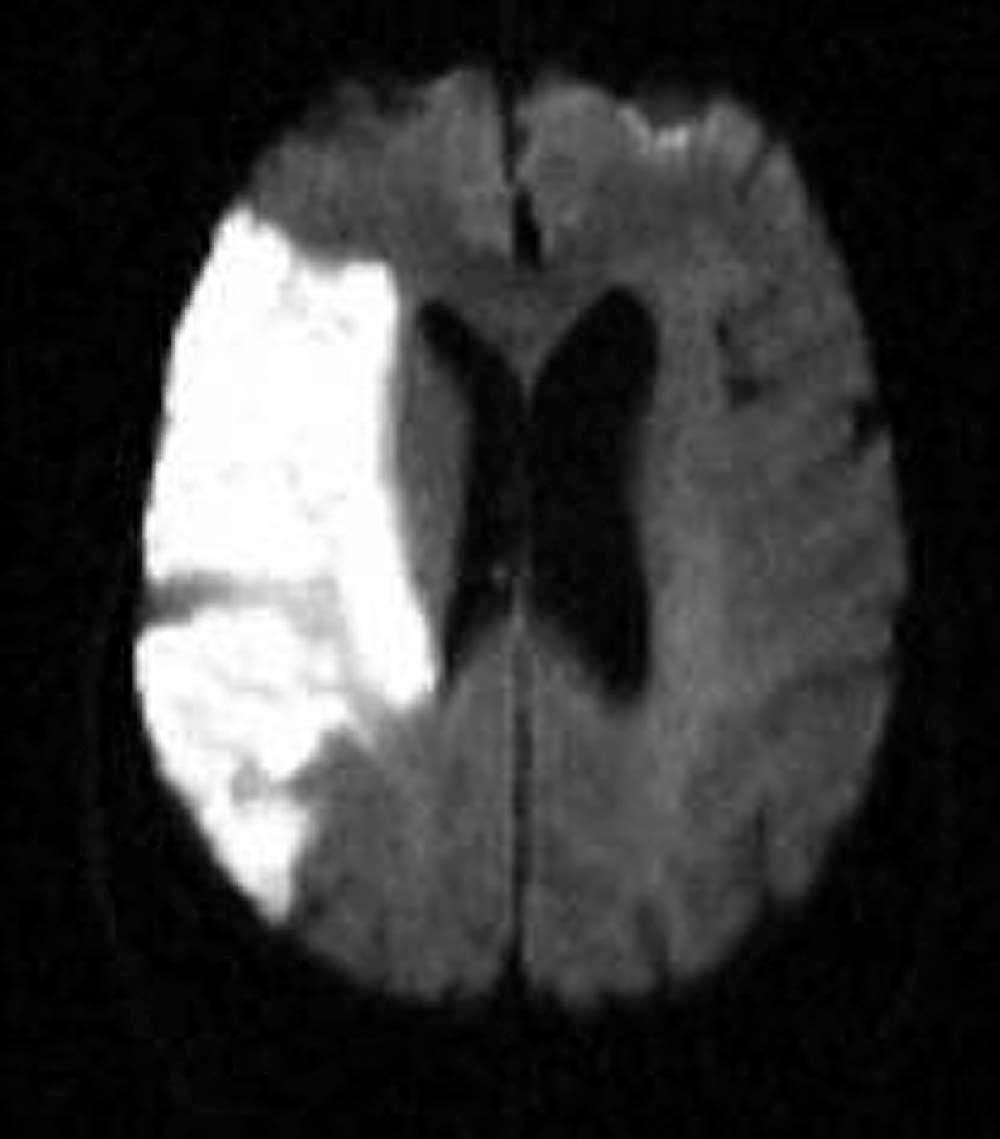

An understanding of stroke is important for psychiatrists for several reasons: it is common, effective treatment is predicated on early recognition, and significant neuropsychiatric sequelae often result from injury to brain parenchyma. Stroke is defined as the acute onset of a neurological deficit due to a cerebro-vascular cause. Strokes may be categorized as ischemic (in which the deficit is caused by blockage of an arterial feeding vessel), which results in a lack of oxygen and metabolic nutrients to the affected territory ( Figure 80-1 ) or hemorrhagic (in which the deficit is caused by vessel rupture). Ischemic strokes occur roughly four times as often as hemorrhagic strokes. Ischemic strokes usually produce focal neurological deficits due to the cessation of blood flow to a specific territory of the brain. In contrast, hemorrhagic strokes, in addition to causing focal deficits, can cause more diffuse symptoms as a result of cerebral edema and an increase in intracranial pressure.

Figure 80-1, Diffusion-weighted MRI of a right middle cerebral artery territory infarct.